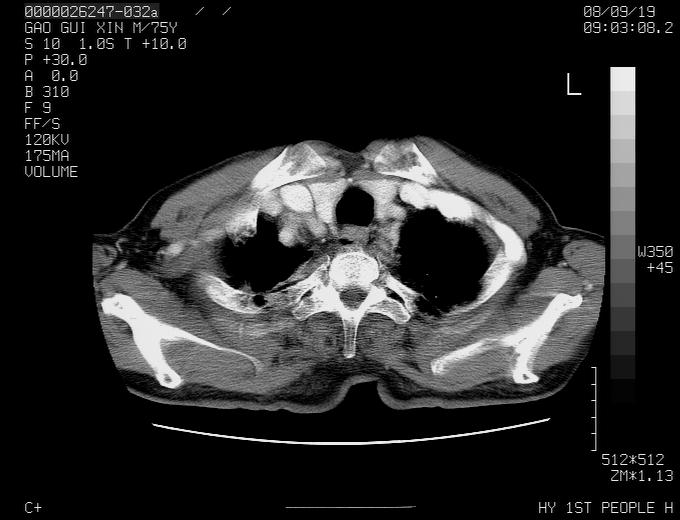

感谢各位老师的意见,左上肺病灶,我本人趋向结核,原因:左上肺见两个类圆形结节,仔细回顾4月份ct似乎原片在该处有条片状密度增高影,强化不明显。

现上传增强片,请各位老师仔细帮我看一下。

右上肺可见条索状影,并可见钙化,左上肺结节可以考虑为结核球,但气管前腔静脉后有肿大淋巴结,本人觉得左上肺结节不能排除转移瘤的可能,右上肺为陈旧性结核灶。

左肺上叶周围性肺癌并纵隔多组lnm.不可能是tb.

左肺上叶尖段瘢痕癌并纵隔淋巴结转移解释更好一些.

左肺周围癌并纵隔淋巴结转移,另一小结节是血管影

左上肺周围型肺癌并纵隔淋巴结转移

1)左肺上叶尖段周围型肺癌并纵隔淋巴结转移。2)冠状动脉及主动脉钙化。